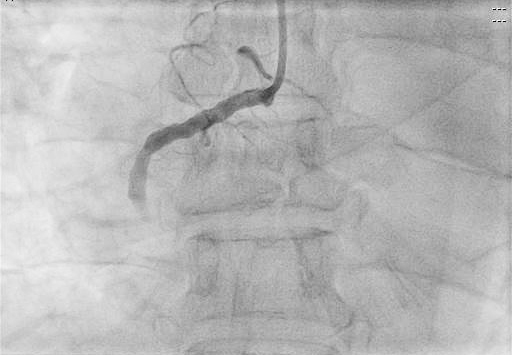

術(shù)前

患者進(jìn)入導(dǎo)管室后,憋喘明顯,血壓、氧飽和度低,需面罩吸氧、大劑量去甲腎上腺素維持血壓。朱宗濤主任建議應(yīng)使用強(qiáng)支撐指引導(dǎo)管,先用軟導(dǎo)絲輕柔操作,結(jié)合血管內(nèi)超聲(IVUS),嘗試尋找血管真腔。術(shù)中選擇6F SAL指引導(dǎo)管行冠狀動(dòng)脈造影提示右冠中段閉塞,先后嘗試Anyreach、Sion工作導(dǎo)絲未能通過閉塞病變,然后在Finecross微導(dǎo)管輔助下,換用Gaia1硬導(dǎo)絲通過閉塞處成功送至右冠遠(yuǎn)端,行血管內(nèi)超聲(IVUS)檢查顯示血管支架遠(yuǎn)段局部夾層、血腫,導(dǎo)絲全程位于血管真腔,在IVUS精確定位下,成功開通血管并植入支架2枚。術(shù)后,經(jīng)CCU醫(yī)護(hù)人員的精心治療,已于10月10日康復(fù)出院。